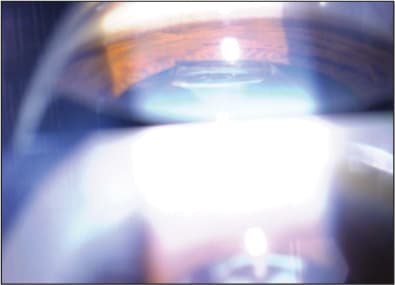

Figures 1 and 2. Bilateral Z syndrome in high myope with gap between implant and posterior capsule. Note severe fibrosis of haptics.

Figure 3. Gonioscopic view of left eye showing severe elevation of inferior haptic above iris plane.